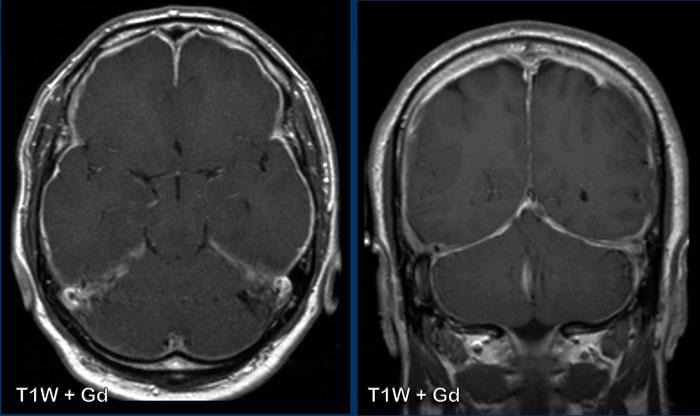

Hình 1

Các dấu hiệu khá tinh tế, nhưng bao gồm:

- Sa thấp trung não với giảm khoảng cách cầu-vú, xóa bể trên hố yên, dẹt phần trước cầu não và gập góc thân não tại chỗ nối sọ-cổ.

- Vùng dưới đồi gập qua mặt lưng hố yên, tuyến yên hơi phì đại (vòng tròn trắng).

- Liên hợp đồi thị bị hạ thấp; phần sau thể chai bị hạ thấp (dấu hiệu “dương vật rũ”). Lưu ý sự dẹt của bể trên tiểu não.

- Trong trường hợp này, amygdale ở vị trí bình thường và không có thoát vị (vòng tròn vàng).

Kết luận: các dấu hiệu điển hình của hạ áp lực nội sọ.